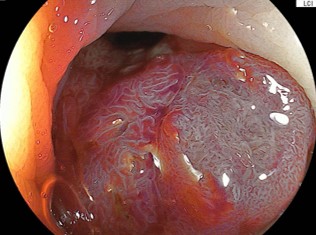

症例1:他院から日帰り内視鏡切除目的で紹介された症例。盲腸に20mm大の平坦な病変を認めます。LST-NG(flat-elevated type)に分類されます。拡大内視鏡では「がん」を疑うVI型ピットパターンを認めませんでした。腺腫病変と考えました。5mm程度の近傍に憩室を合併しております。無条件で内視鏡的粘膜下層剥離術(ESD)を適応している施設も多いかと思います。しかし、このような病変は、線維化(:粘膜下層の線維が密に増生していること、しばしば内視鏡治療の困難性を引き起こします)がなければESDの適応などないのです。当院では、内視鏡的粘膜切除術(EMR)により平坦な病変であっても30mm弱程度までは適応としていることが多いです。最終病理診断:高異型度腺腫で切除断端陰性で治癒切除(ちゆせつじょ:取り切れて治っていること)でした。術後も偶発症を認めませんでした。

粘膜下層に局注して、挙上がえられれば内視鏡的粘膜切除術(EMR)の適応となります。